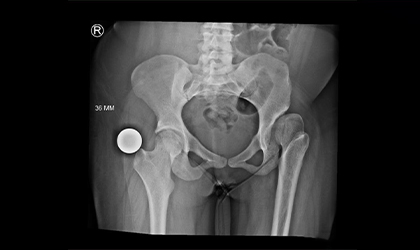

Performing over 500 hip surgeries, Dr. Bipin Theruvil demonstrates extensive expertise in orthopedics. His surgical experience encompasses various procedures such as hip replacement, hip arthroscopy, and fracture repair, ensuring patients receive high-quality care for a range of hip conditions. Dr. Theruvil's proficiency and dedication to advancing surgical techniques contribute to successful outcomes and improved quality of life for his patients.

Explore real-world examples of successful surgical interventions by Dr. Bipin Theruvil. These cases highlight innovative techniques and personalized care that have transformed patients' lives.

Each case study provides detailed insights into the challenges faced, approach taken, and outcomes achieved, demonstrating Dr. Theruvil's expertise in hip and knee replacements.Each case study provides detailed insights into the challenges faced, approach taken, and outcomes achieved, demonstrating Dr. Theruvil's expertise in hip and knee replacements.Each case study provides detailed insights into the challenges faced, approach taken, and outcomes achieved, demonstrating Dr. Theruvil's expertise in hip and knee replacements.